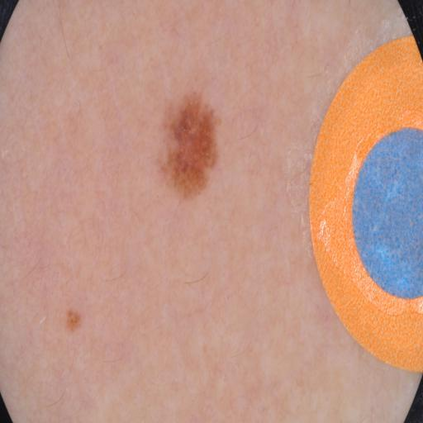

Skin lesion segmentation from dermoscopy images is of great significance in the quantitative analysis of skin cancers, which is yet challenging even for dermatologists due to the inherent issues, i.e., considerable size, shape and color variation, and ambiguous boundaries. Recent vision transformers have shown promising performance in handling the variation through global context modeling. Still, they have not thoroughly solved the problem of ambiguous boundaries as they ignore the complementary usage of the boundary knowledge and global contexts. In this paper, we propose a novel cross-scale boundary-aware transformer, \textbf{XBound-Former}, to simultaneously address the variation and boundary problems of skin lesion segmentation. XBound-Former is a purely attention-based network and catches boundary knowledge via three specially designed learners. We evaluate the model on two skin lesion datasets, ISIC-2016\&PH$^2$ and ISIC-2018, where our model consistently outperforms other convolution- and transformer-based models, especially on the boundary-wise metrics. We extensively verify the generalization ability of polyp lesion segmentation that has similar characteristics, and our model can also yield significant improvement compared to the latest models.